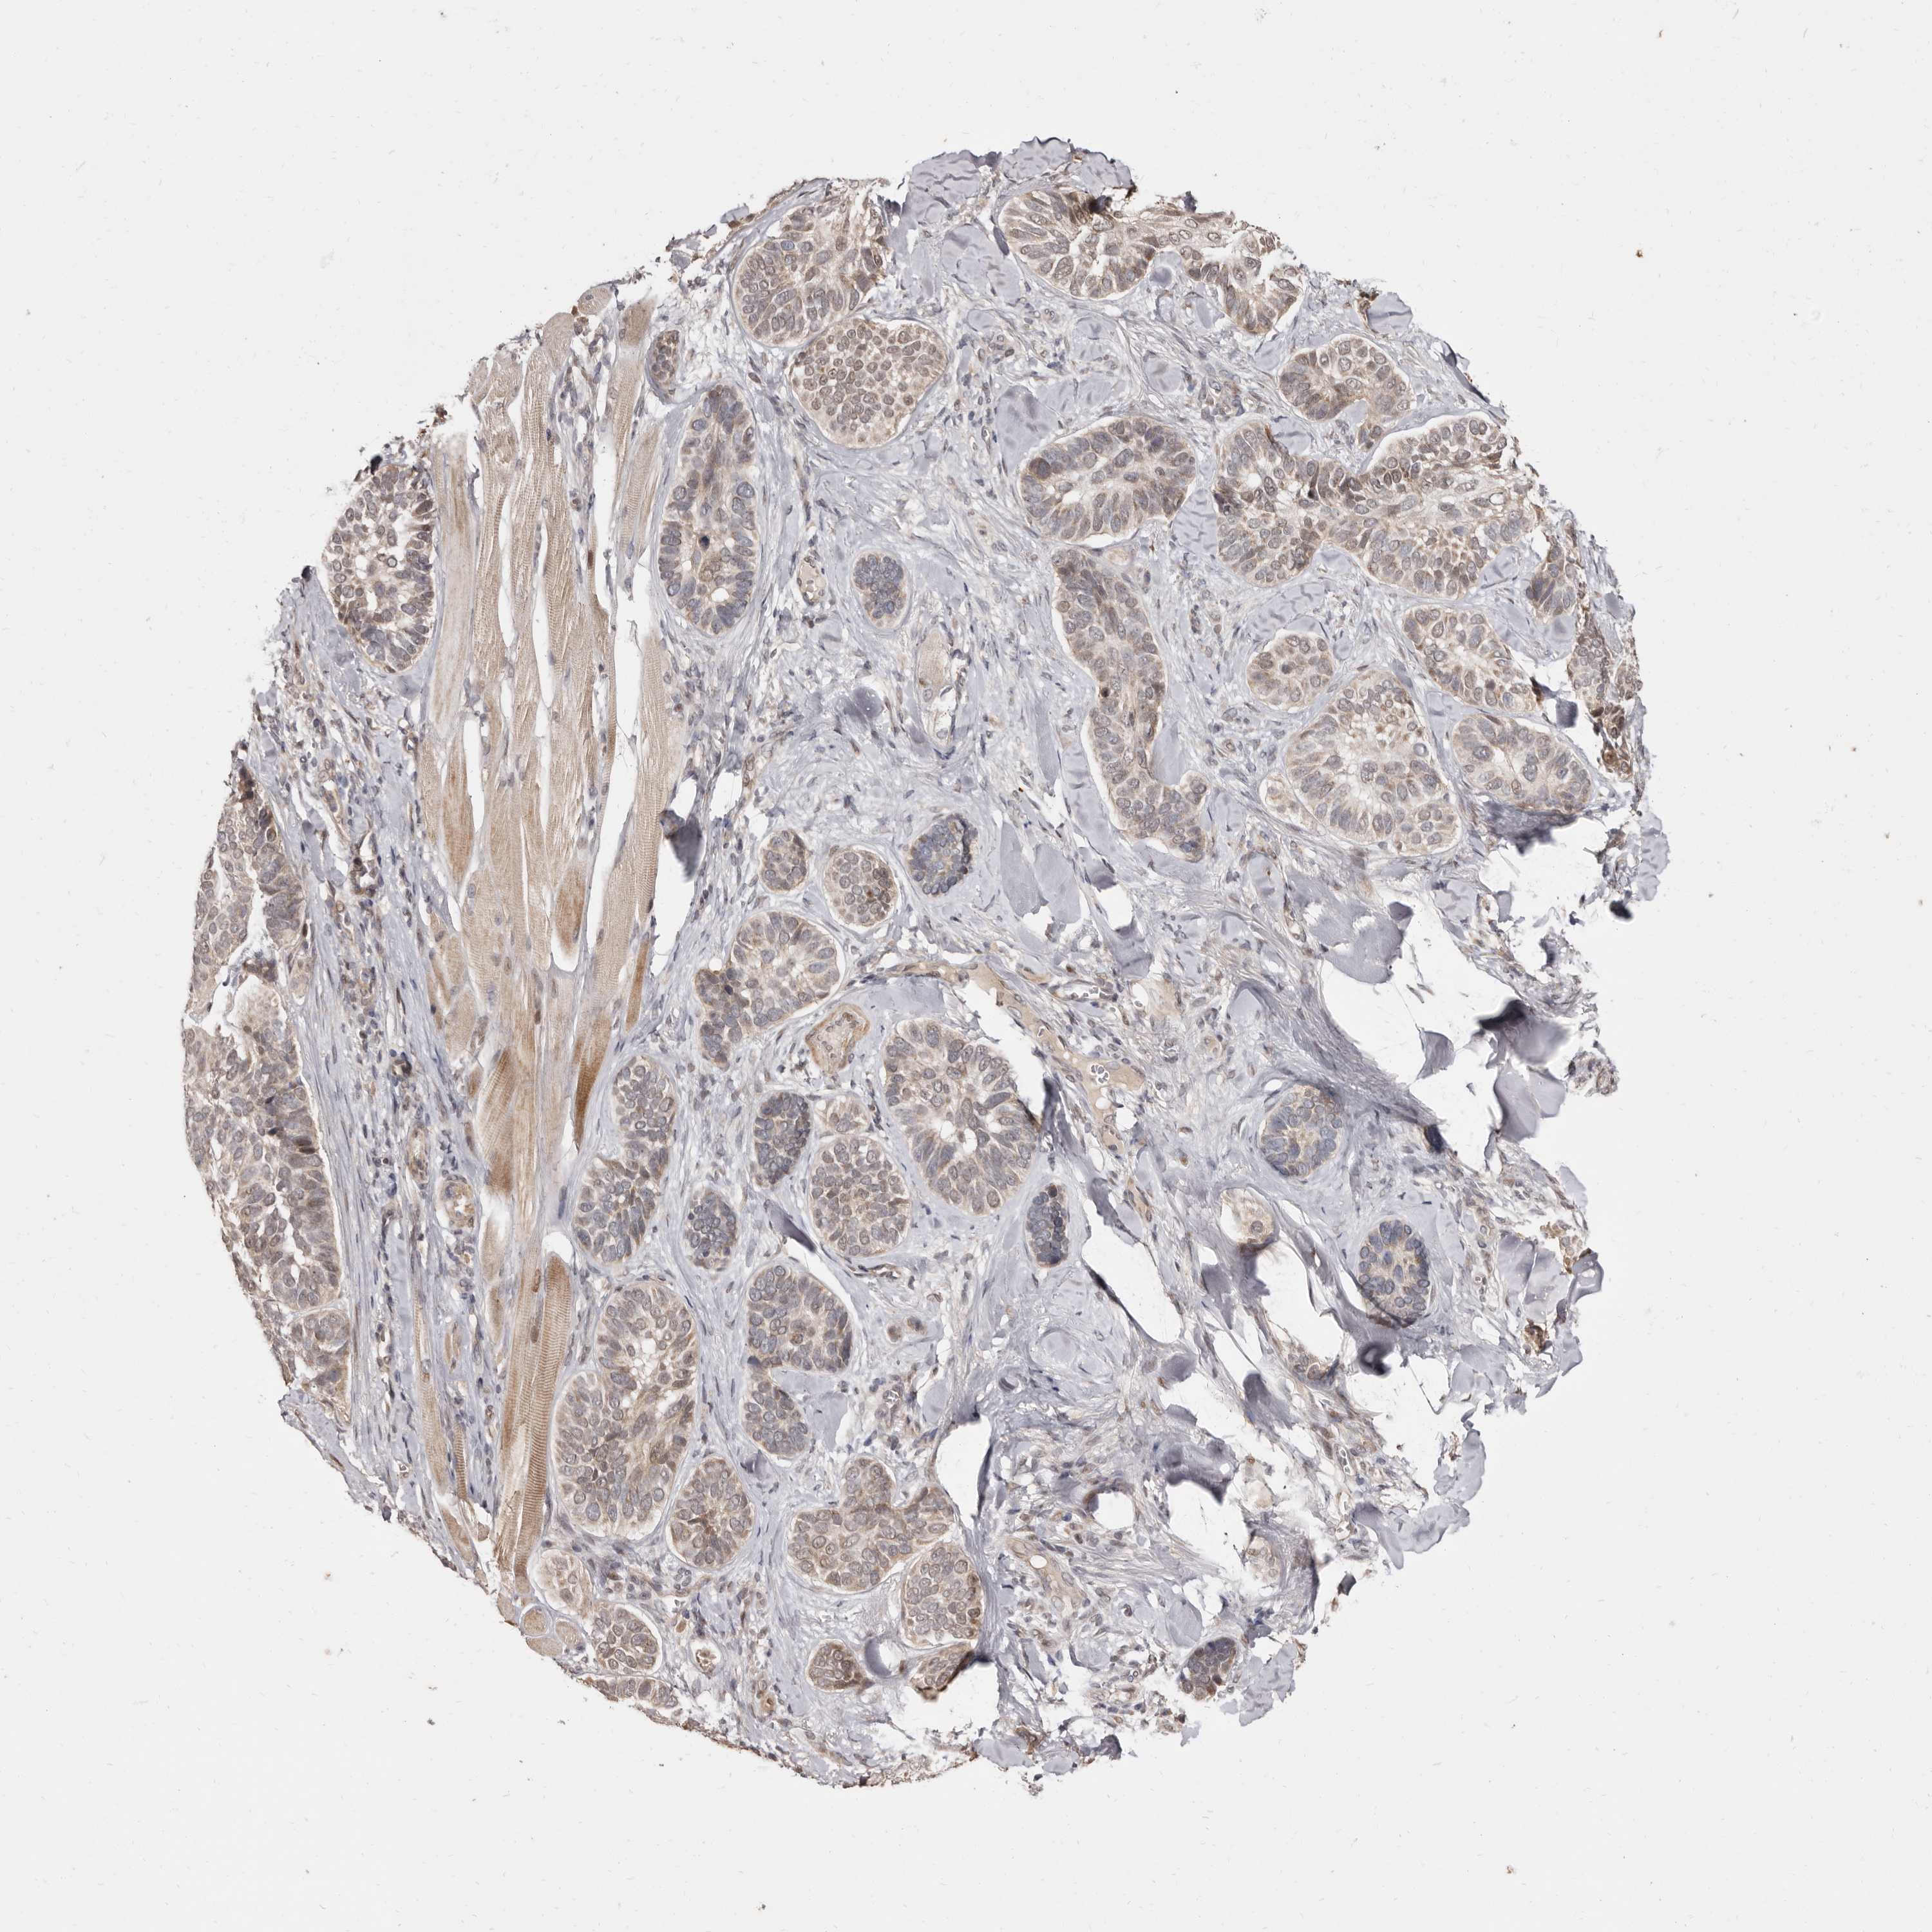

SKIN CANCER - Protein expressioni

A mouse-over function shows sample information and annotation data. Click on an image to view it in a full screen mode. Samples can be filtered based on level of antibody staining by selecting one or several of the following categories: high, medium, low and not detected. The assay and annotation is described here.

Antibody stainingi

Antibody staining in the annotated cell types in the current human tissue is reported as not detected, low, medium, or high, based on conventional immunohistochemistry profiling in selected tissues. This score is based on the combination of the staining intensity and fraction of stained cells.

Each image is clickable and will lead to virtual microscopy that enables deeper exploration of all samples and also displays staining intensity scores, fraction scores and subcellular localization as well as patient and tissue information for each sample.

Antibody HPA028466

Squamous cell carcinoma, NOS